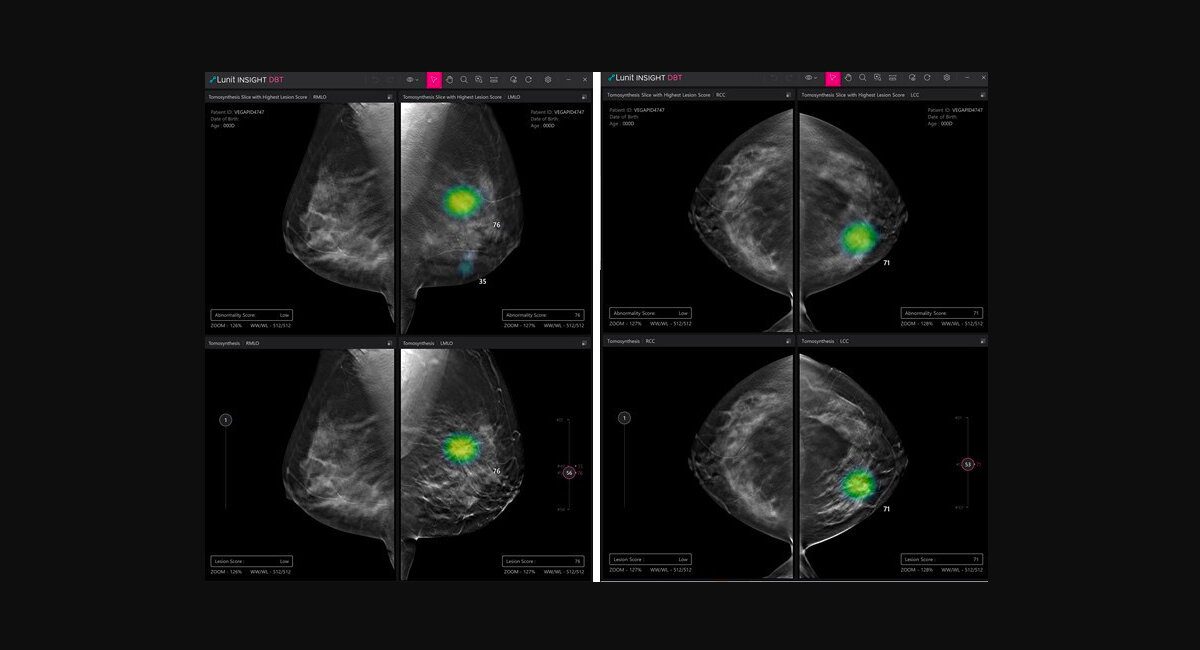

Roundup: Lunit gets new CE mark for AI DBT solution and more briefs

Lunit obtains new CE mark for AI DBT solutionSouth Korean medical AI company Lunit has received a CE mark under Europe’s latest Medical Device Regulation for its AI software for digital breast tomosynthesis (DBT)…